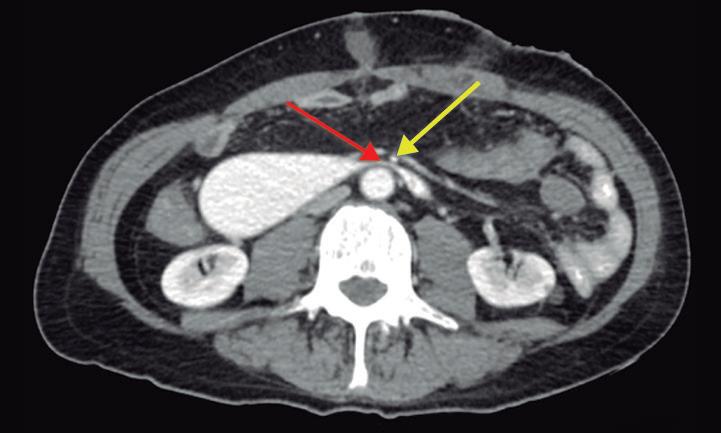

Paciente con vómitos en el periodo posoperatorio

Germán Francisco Rojas, Gabriel Adrián Mariño Camacho, Jesica Antonella Andruetto, Martín José Drago, Alejandro Moreira Grecco, Mariano Volpacchio, Esteban González Ballerga